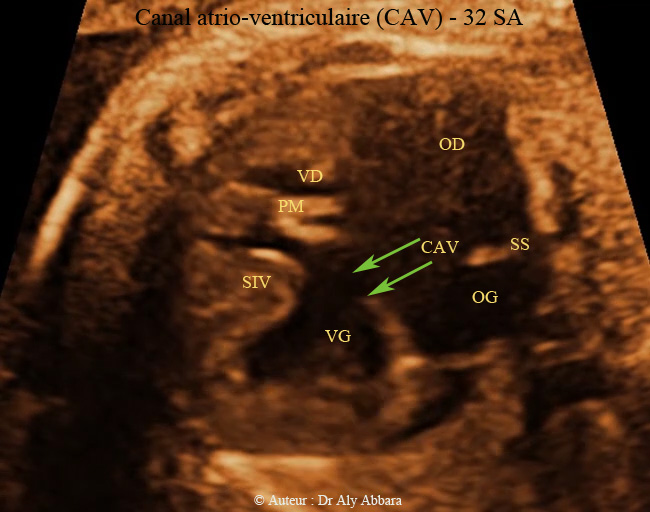

Vidéo et image échographiques cardiaques montrant la présence de :

- un canal atrio-ventriculaire (CAV) complet.

- une valve atrio-ventriculaire (VAV) commune, unique, à une ouverture diastolique satisfaisante vers deux ventricules avec prédominance gauche (ventricule gauche "VG" et ventricule droit "VD" séparés pareillement par le septum interventriculaire "SIV" musculaire incomplet).

- une communication inter-auriculaire (CIA) de type ostium primum large aboutissant à la constitution d'une oreillette unique ou quasi unique (petit septum secundum "SS" au dôme de l'oreillette commune).

- Pas de valve de Vieussens battant dans le secteur gauche de l'oreillette unique.

- une communication interventriculaire (CIV) de taille moyenne ; il s'agit d'une communication de type de CIV d'admission.

- On observe également sur cette image la plaque modératrice (PM) battant dans le ventricule droit.

- Rythme cardiaque régulier, avec liaison auriculo-ventriculaire 1/1 à 128 bpm.

Fœtus âgé de 32 SA trisomique 21 (47,XY + 21 - trisomie 21 libre).